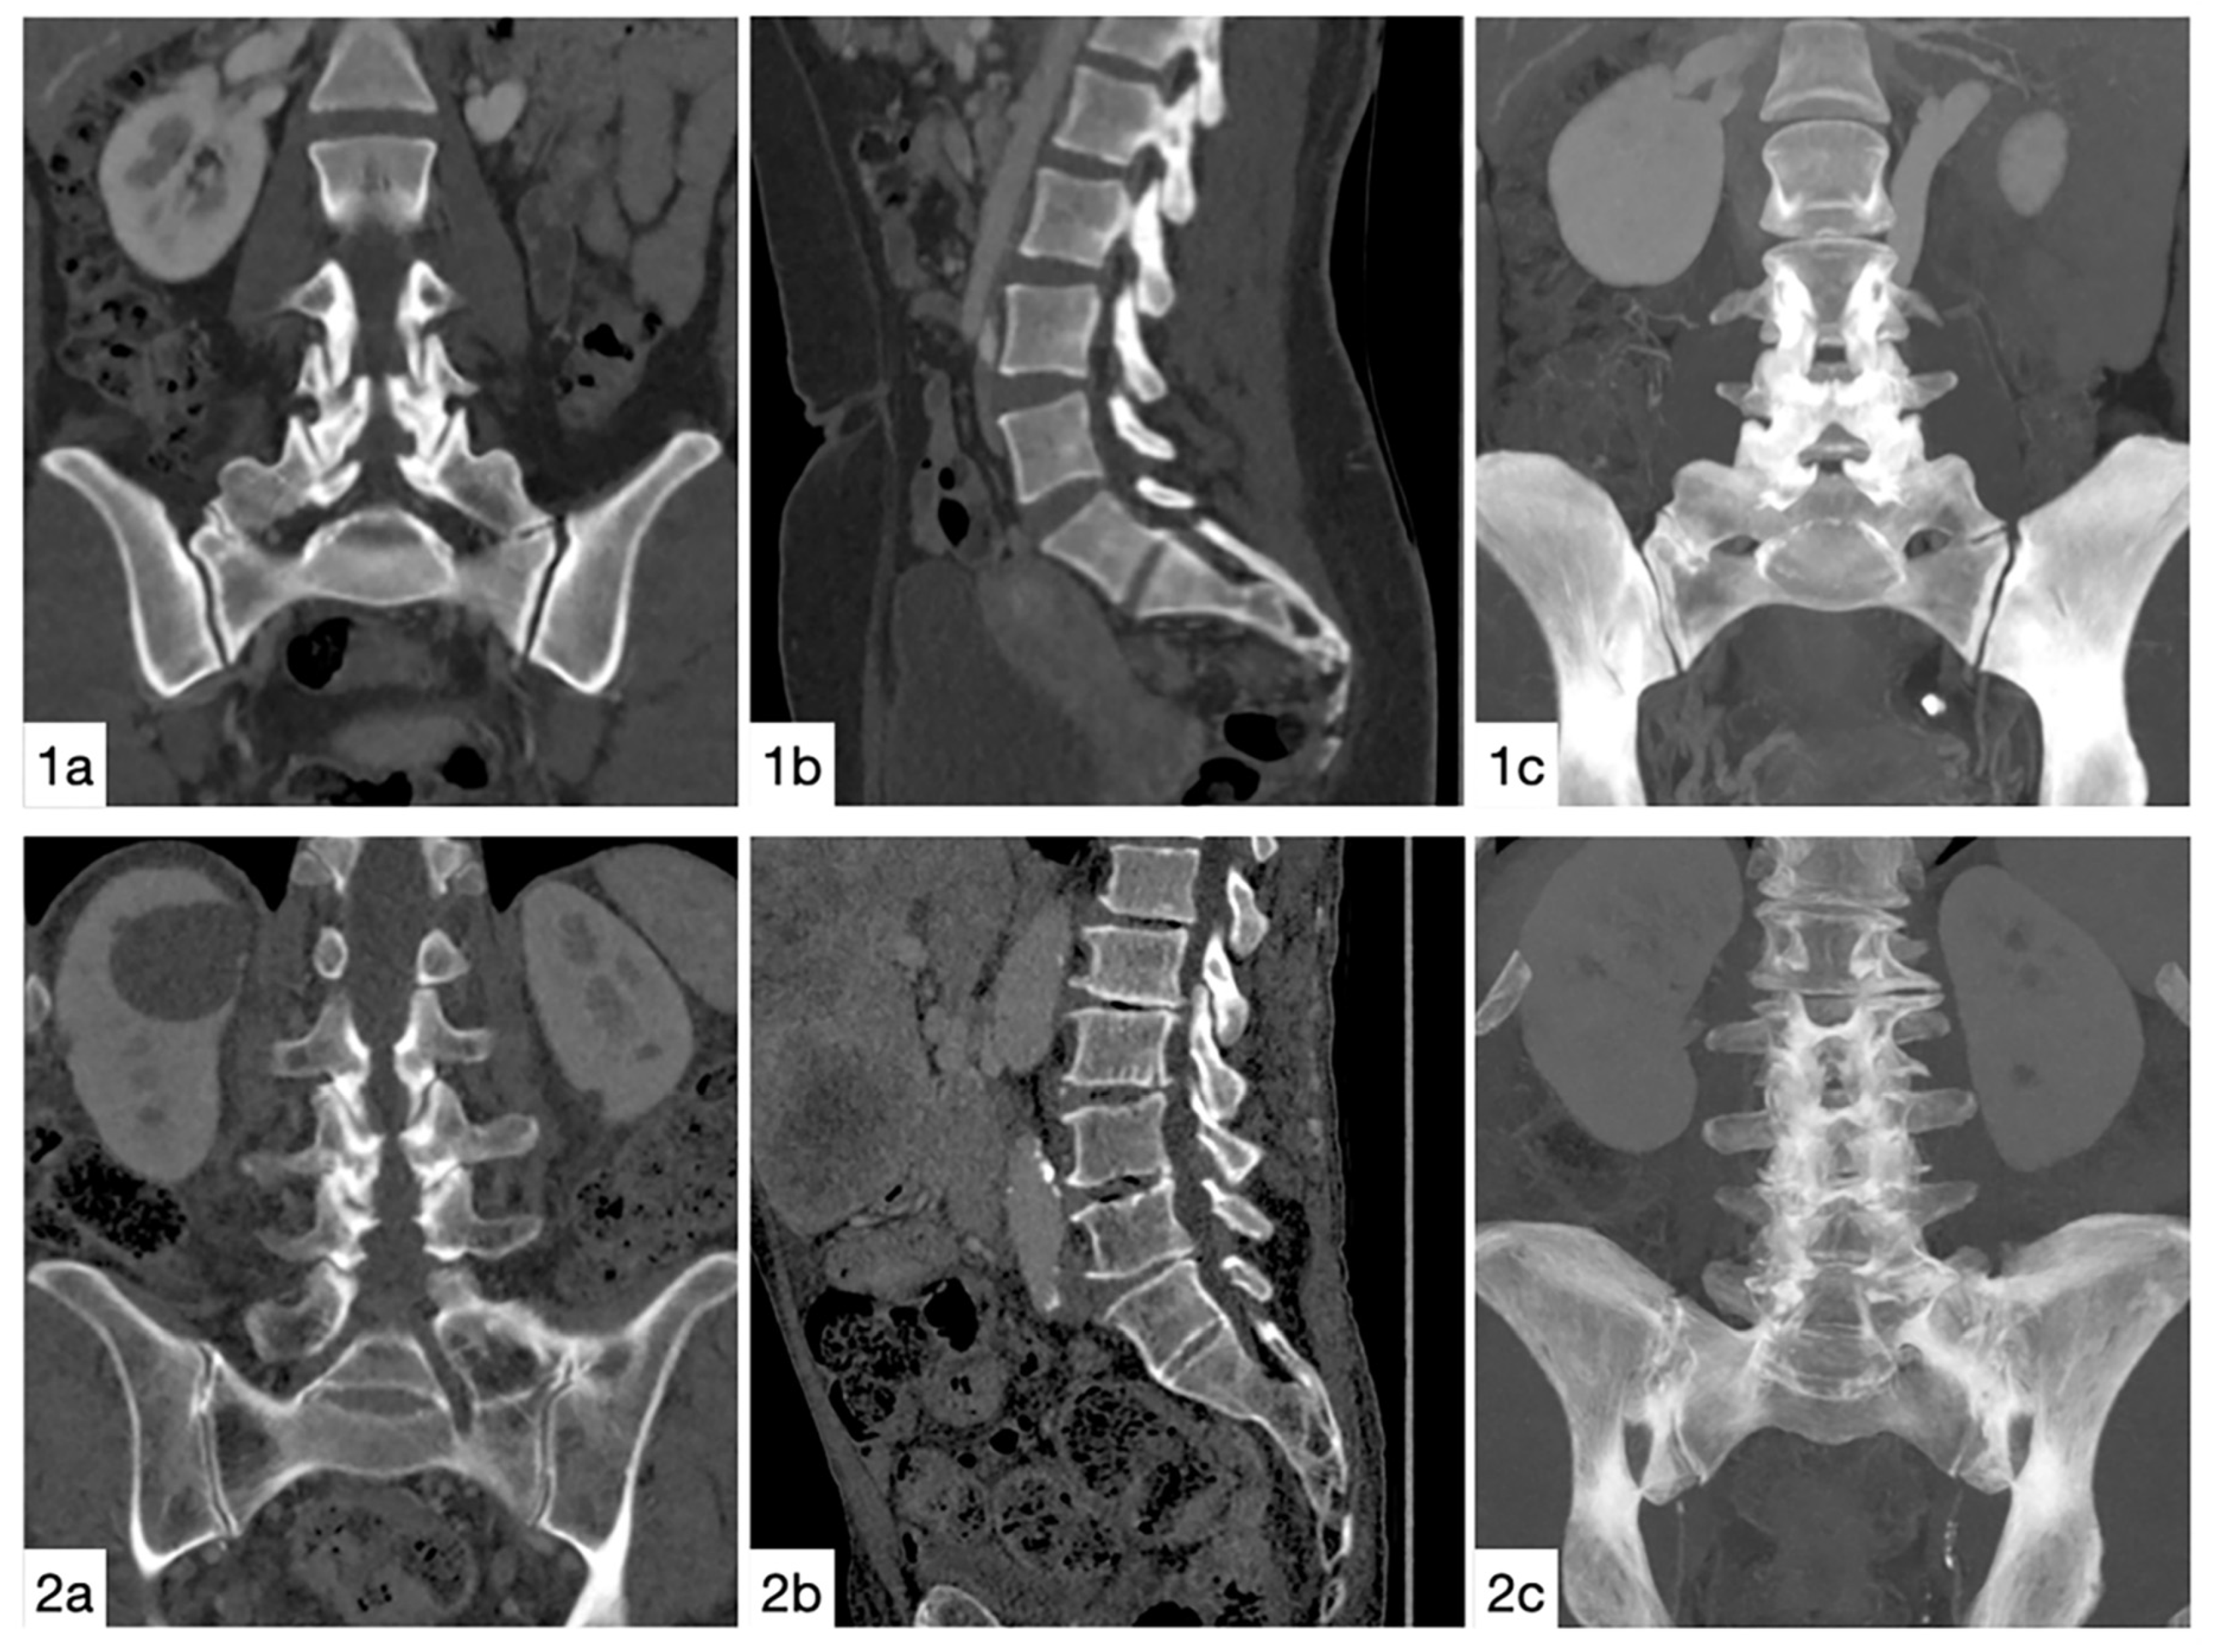

2. Materials and Methods

2.1. Individuals

2.2. Image Assessment